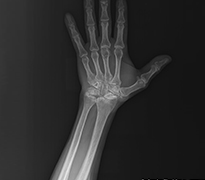

El ve kol eklemlerinde kireçlenme, eklem yüzeyini oluşturan kıkırdak yapının zamanla bozulmasıyla ortaya çıkan dejeneratif bir durumdur. En sık parmak eklemlerinde, başparmak kökünde ve el bileğinde görülür. Hastalarda ağrı, hareket sırasında hassasiyet, tutukluk ve zamanla şekil değişiklikleri gelişebilir. Kavrama gücünde azalma ve ince işlerde zorlanma da sık karşılaşılan şikayetler arasındadır. Bu durum sadece yaşa bağlı değil, travmalar sonrasında da gelişebilir. Özellikle skafoid kırığı sonrası uygun tedavi edilmezse el bileğinde zamanla kireçlenme ortaya çıkabilir.

Skafoid Kaynamama Sebebiyle El Bileği Kireçlenmesi (SNAC)

Skafolunat Bağ Yırtığı Sebepli El Bileği Kireçlenmesi (Slac)